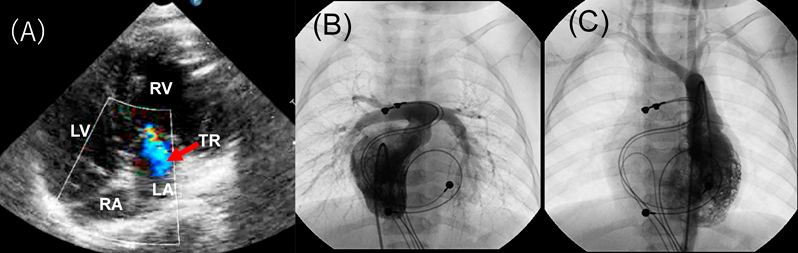

心エコー検査:三尖弁輪径13.5 mm(91% of normal),僧帽弁輪径16.7 mm(121% of normal),VSD 14×20 mm(Fig. 4).

Fig. 4 Four chamber view of echocardiography

LA, left atrium; LV, left ventricle; RA, right atrium; RV, right ventricle.